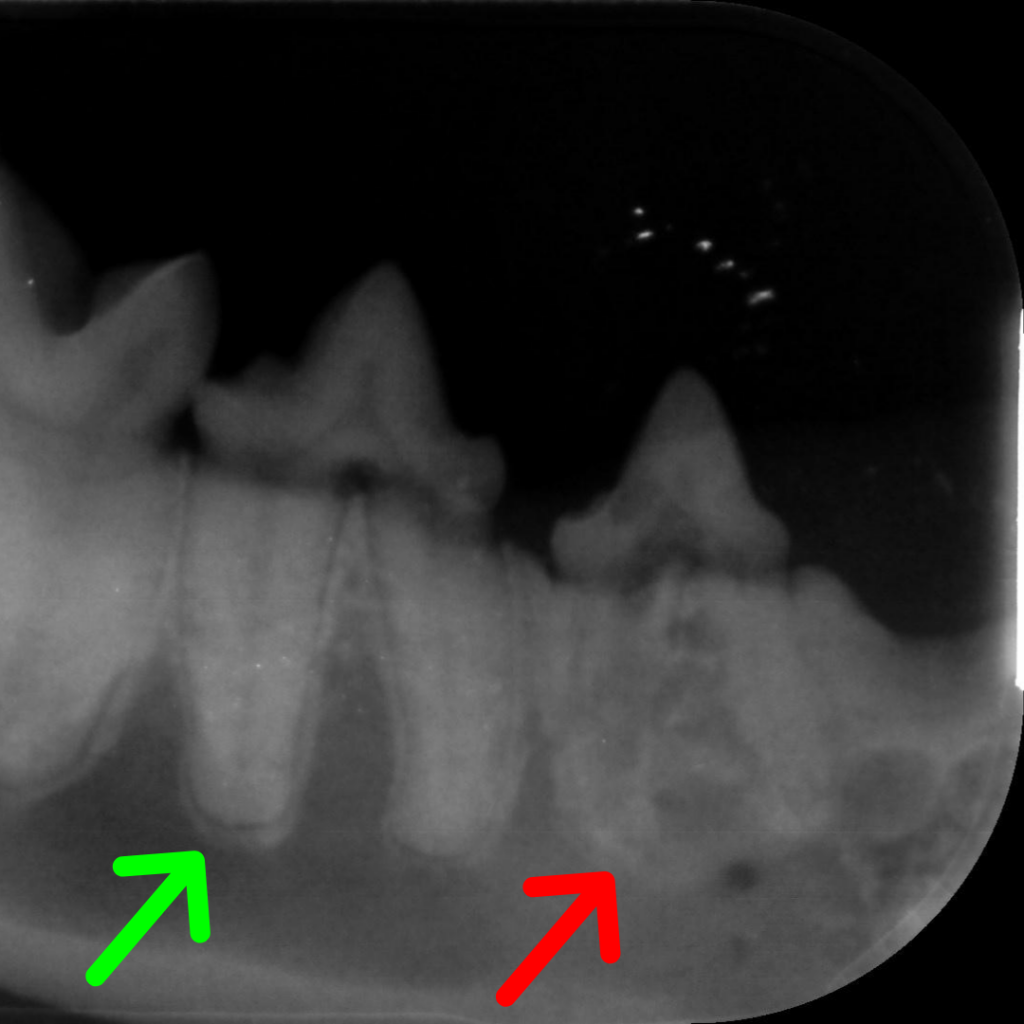

Still other times, we notice gingivitis or periodontal disease and recommend a dental. It isn’t until we are taking dental X-rays of your pets mouth that we pick up that there may be resorptive lesions, as the entire lesion can occur under the gumline.

Often when the lesion is under the gum, the tooth becomes replaced with bone, and the X-rays no longer show the normal periodontal ligament around the tooth. Instead the tooth root blends into the bone around it (see Green Arrows for normal periodontal ligaments.)

Type 2 lesions involve the root below the gumline being resorbed and then gradually replaced with bone. The periodontal ligament is lost and the root can become difficult to distinguish from the bone around it.